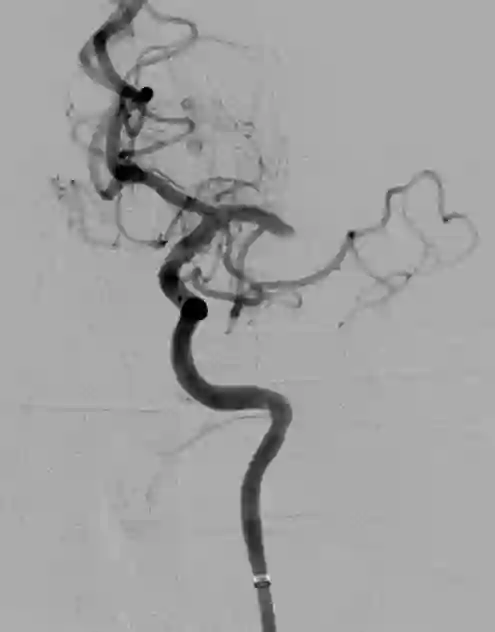

Objective: The objective of this work is to introduce and demonstrate the effectiveness of a novel sensing modality for contact detection between an off-the-shelf aspiration catheter and a thrombus. Methods: A custom robotic actuator with a pressure sensor was used to generate an oscillatory vacuum excitation and sense the pressure inside the extracorporeal portion of the catheter. Vacuum pressure profiles and robotic motion data were used to train a support vector machine (SVM) classification model to detect contact between the aspiration catheter tip and a mock thrombus. Validation consisted of benchtop accuracy verification, as well as user study comparison to the current standard of angiographic presentation. Results: Benchtop accuracy of the sensing modality was shown to be 99.67%. The user study demonstrated statistically significant improvement in identifying catheter-thrombus contact compared to the current standard. The odds ratio of successful detection of clot contact was 2.86 (p=0.03) when using the proposed sensory method compared to without it. Conclusion: The results of this work indicate that the proposed sensing modality can offer intraoperative feedback to interventionalists that can improve their ability to detect contact between the distal tip of a catheter and a thrombus. Significance: By offering a relatively low-cost technology that affords off-the-shelf aspiration catheters as clot-detecting sensors, interventionalists can improve the first-pass effect of the mechanical thrombectomy procedure while reducing procedural times and mental burden.